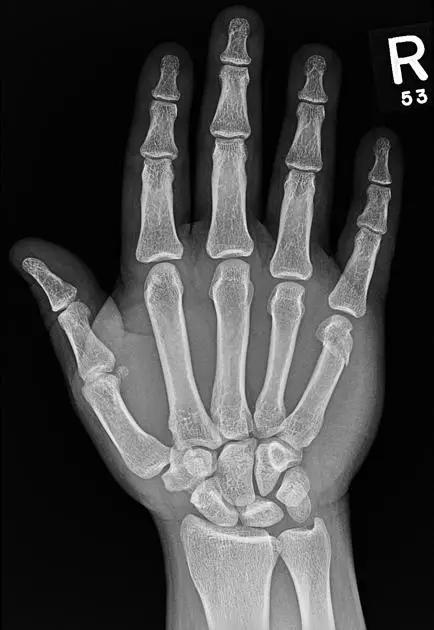

7. Boxer's 骨折

第 5 掌骨颈骨折伴有掌骨头向掌侧移位。

(来源:Radiopaedia)